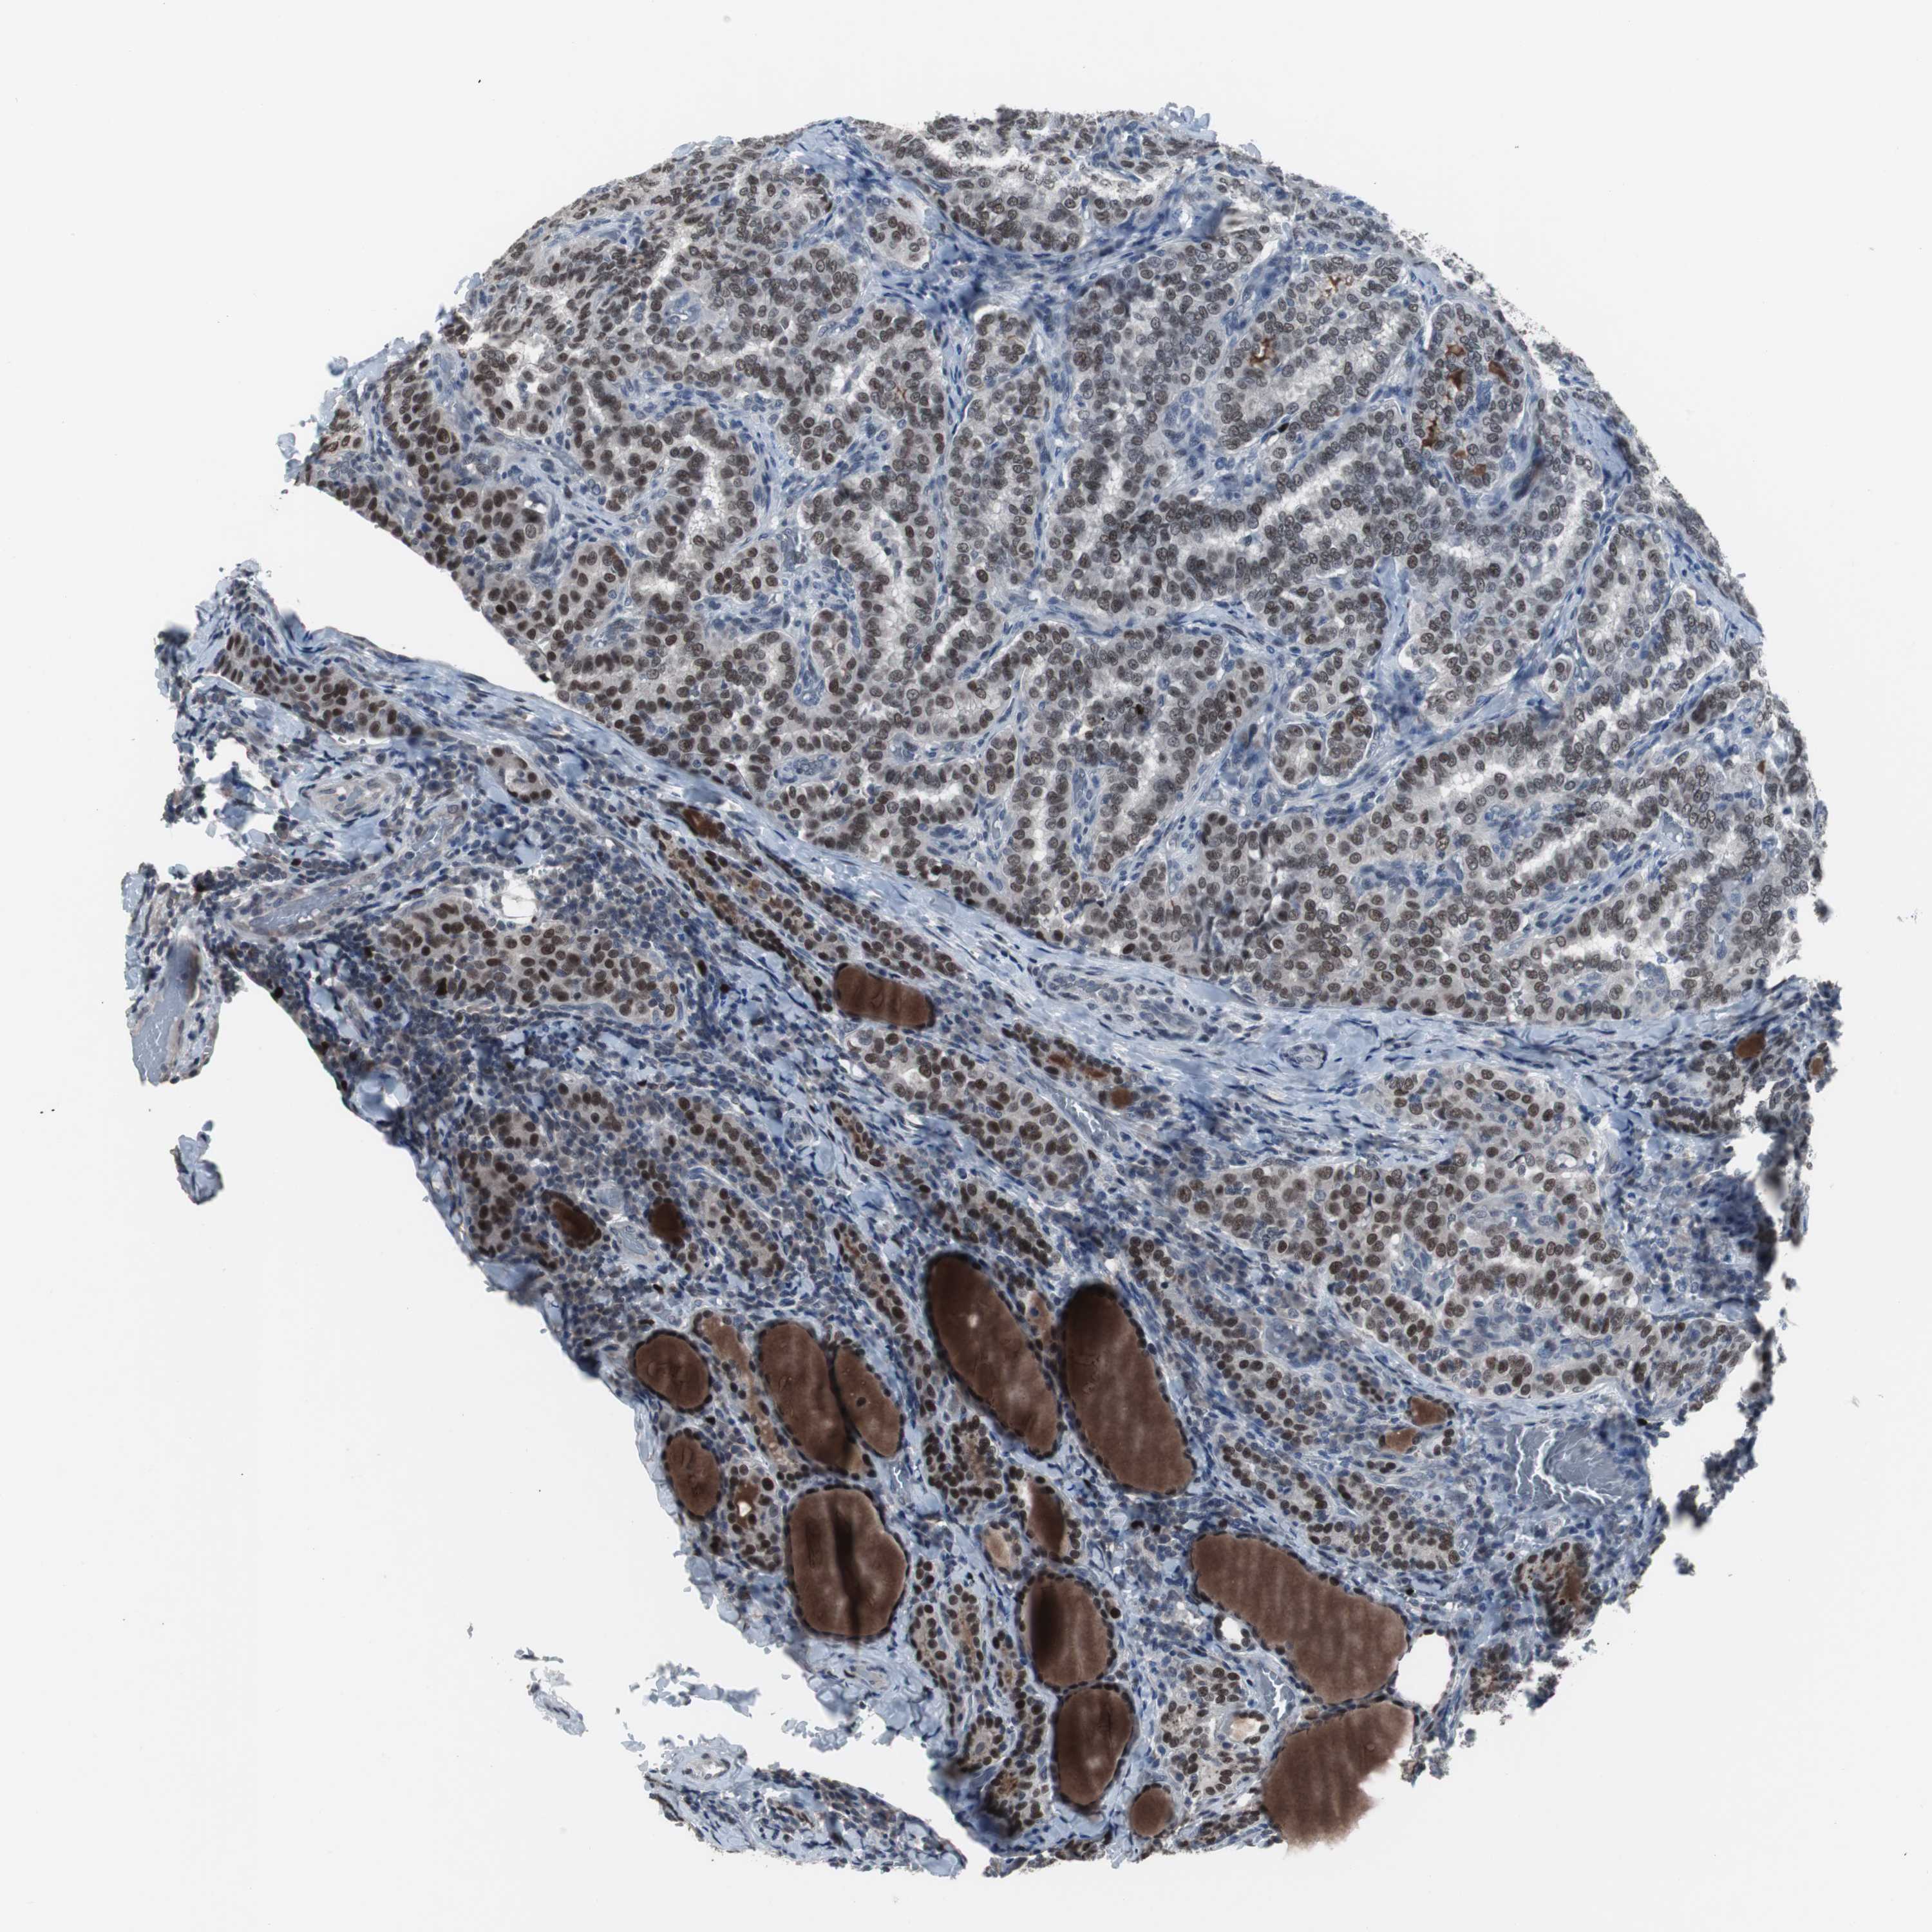

THYROID CANCER - Protein expressioni

A mouse-over function shows sample information and annotation data. Click on an image to view it in a full screen mode. Samples can be filtered based on level of antibody staining by selecting one or several of the following categories: high, medium, low and not detected. The assay and annotation is described here.

Note that samples used for immunohistochemistry by the Human Protein Atlas do not correspond to samples in the TCGA dataset.

Antibody stainingi

Antibody staining in the annotated cell types in the current human tissue is reported as not detected, low, medium, or high, based on conventional immunohistochemistry profiling in selected tissues. This score is based on the combination of the staining intensity and fraction of stained cells.

Each image is clickable and will lead to virtual microscopy that enables deeper exploration of all samples and also displays staining intensity scores, fraction scores and subcellular localization as well as patient and tissue information for each sample.

Antibody HPA007176

Staining

High

Medium

Low

Not detected

Intensity

Strong

Moderate

Weak

Negative

Quantity

>75%

75%-25%

<25%

None

Location

Nuclear

Cytoplasmic/membranous

Cytoplasmic/membranous,nuclear

Papillary adenocarcinoma, NOS

Follicular adenoma carcinoma, NOS